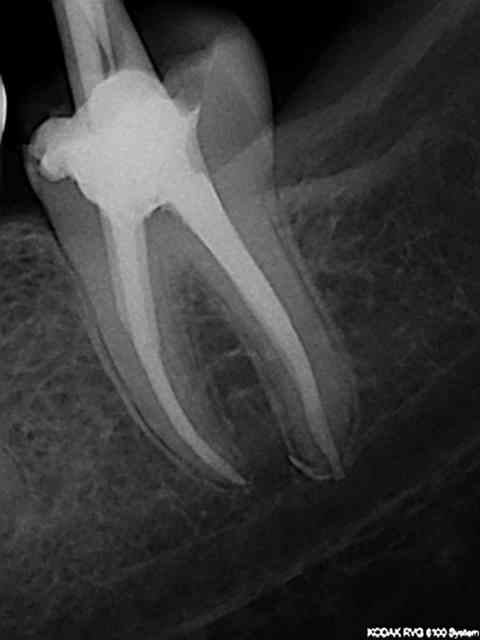

"dit chicot 29 , c'est alesé avec des instruments de quelle taille ces canaux?"

Sx protaper, largo numero 3, re sx pour se rapprocher de l'apex puis s1, s2, f1 f2 protapers. Depuis 4 mois j'ai remplacé s2, f1 f2 par r25 réciproc voir r40.

Ce matin finition r40, pas d'empreinte pour ic, je ne disposais que d'une demi-heure et devis non établi.

Fuck j'arrive pas à virer la radio avec l'inlay core.

J'aime bien le IC sur la pré-molaire

1. c'est une 6, 2. c'est pas une de mes réalisations et ça a au moins 12 ans, comme quoi !